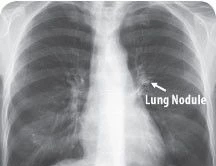

目前,传统检测方法仍无法发现肺部40毫米大小的结节,因此肺癌患者死亡率高达90%。惊喜的是,Enlitic开发的系统能发现小于5毫米的结节,使患者的生存率能增加10倍。

图中箭头所指为肺结节(Lung Nodule)